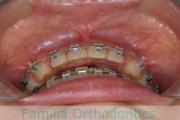

No.23V-100

- 上顎前突

- 叢生

- 14歳

- 女性

- 上:

- 44

- 下:

- 55

- 主な使用装置:

- FEA

歯並びを治したいということで来院されました。下あごがやや右側に偏位して後退している、上顎前突(出っ歯)でした。上下左右から小臼歯を抜歯して、歯科矯正用アンカースクリューを併用したマルチブラケット法にて治療を行いました。約2年、24回の来院をしていただきました。

下顎の後退はいびきなどの上部気道の障害が出やすいと考えられます。